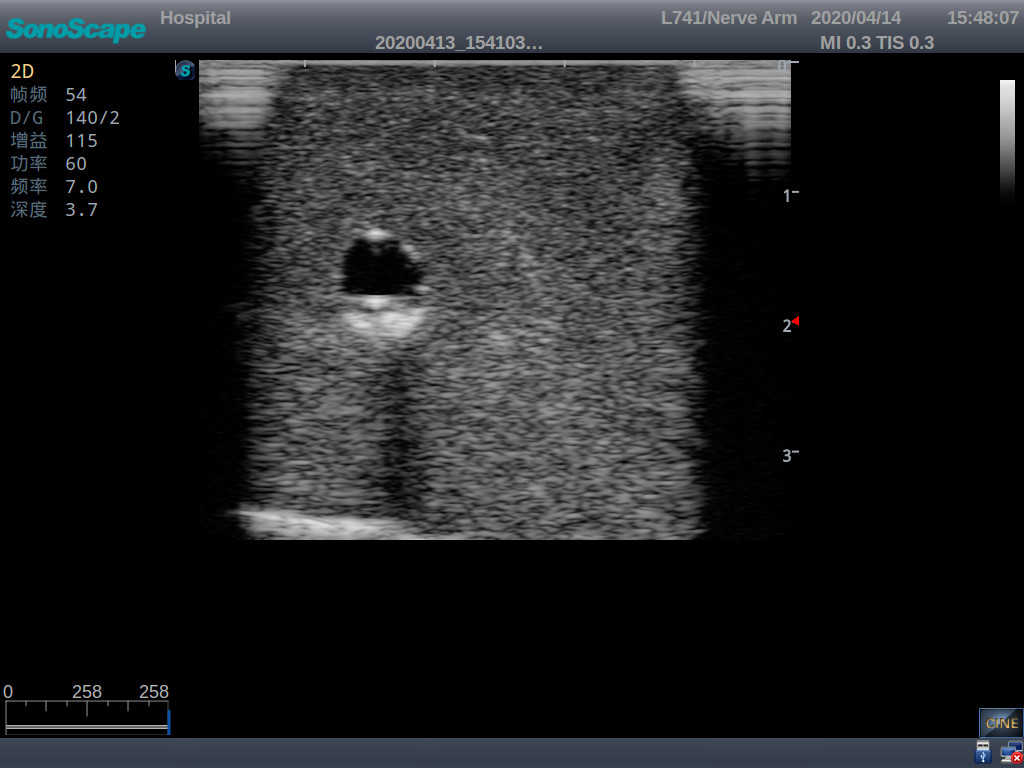

2)   It can be used by real ultrasound machines

3)   Clear and real images of the tissues and organs (basilic vein and superior vena cava)

4)   When conducting vascular puncture, the piercing can be truly felt, and venous blood outflow can be seen